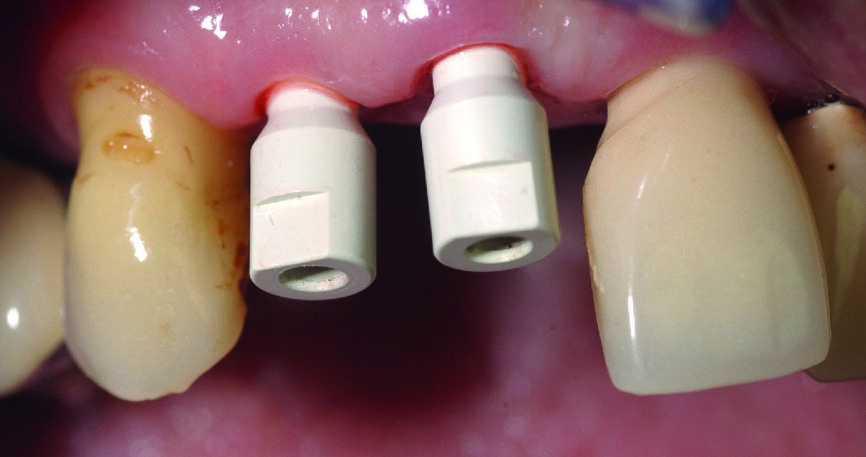

Figs. 11a & b : Vues cliniques et occlusales des scan bodies en place. Notez les positions et les axes obtenus, qui faciliteront les réalisations prothétiques définitives.

L’intervention est programmée en février 2019. Des implants de type Avinent Ocean hexagone interne sont poses. Afin de sécuriser la pose des implants et assurer l’assainissement du site, un lambeau est réalisé après l’extraction des deux dents. Toute la séquence de forage ainsi que la pose des implants sont passés à travers les douilles du guide chirurgical. L’indexation doit être bien respectée en alignant les repères présents sur le guide avec ceux du porte implant.

Les implants sont vissés à la main à l’aide d’une clé dynamométrique. Nous vissons ensuite les piliers temporaires (Avinent), et les couronnes provisoires en résine PMMA sont rebasées et scellées (laboratoire Crown Ceram) avant de suturer le lambeau. À ce stade, notons que le second avantage du lambeau est de pouvoir aussi contrôler parfaitement l’adaptation prothétique, et d’éviter toute fusée de ciment de scellement. Une radio de contrôle postopératoire est réalisée (Fig. 7).

Des scan bodies (Core 3D), correspondant aux implants, sont positionnés et les empreintes optiques réalisées avec la camera 3Shape (Figs. 11a et b). A ce stade, il est fortement recommandé de faire une radiographie de contrôle, afin de vérifier le bon enfoncement des scan bodies et pour éviter toute erreur, qui se répercuterait au niveau de la prothèse (Fig. 12).